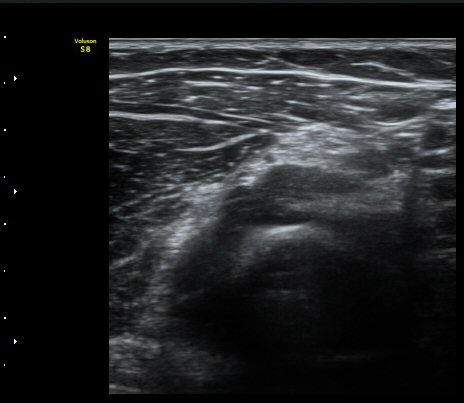

ÃÊÀ½ÆÄ °Ë»ç